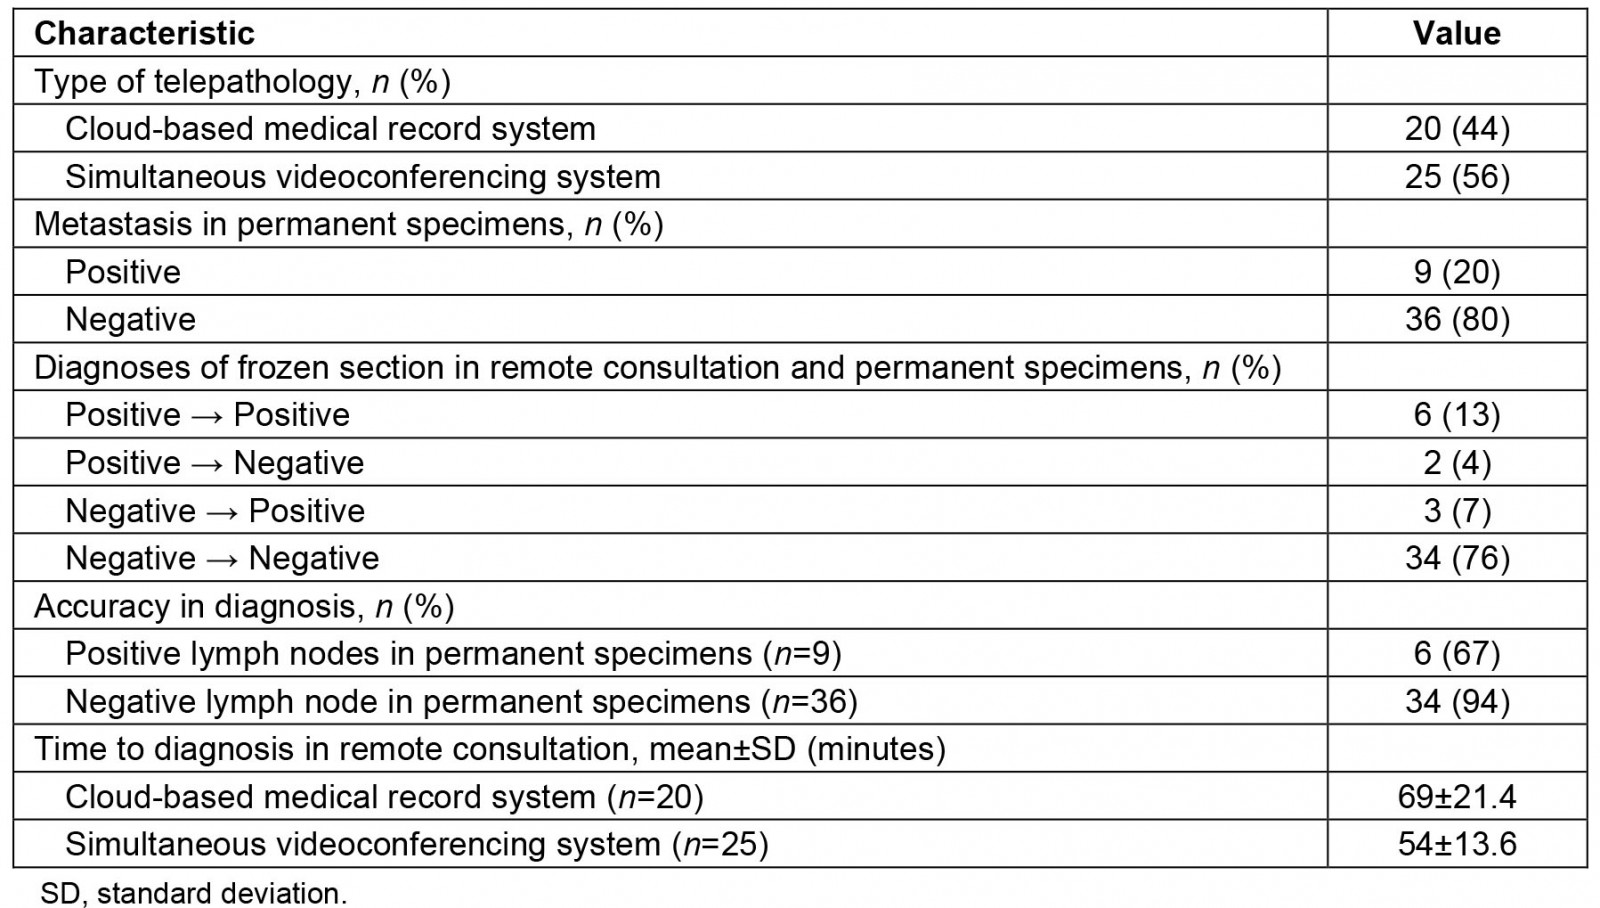

Table 3 shows the features of the sentinel lymph node biopsies including findings. In total, the surgeries of 20 patients (44%) and 25 patients (56%) involved consultation of the cloud-based medical record system and the simultaneous videoconferencing system, respectively.

Among these, positive and negative cases in the remote consultations were 8 (18%) and 37 (82%), respectively. Compared to the permanent specimens, the overall accuracy ratio was 89% (40/45), with the positive and negative predictive values being 67% (6/9) and 94% (34/36). Supplementary table 1 shows breakdowns of cases where paraffin section and frozen section of sentinel lymph nodes differed. An illustrative example of these discrepancies is shown in Figure 1, where a false positive diagnosis occurred during a remote intraoperative frozen section consultation of a sentinel lymph node biopsy. Upon review of this case, it was determined that prominent histiocytic proliferation had been mistakenly identified as cancer cells.

We reviewed a total of four out of the five cases for which there were discrepancies between diagnosis of paraffin section and frozen section of sentinel lymph nodes. After the review, it was determined that there were no differences in diagnosis between the digital and traditional frozen sections of sentinel lymph nodes (Supplementary table 1). Furthermore, both the quality of the frozen sections and the images obtained from the monitor for the digital slides were excellent. There were no issues such as tissue wrinkles, tissue overlap, tissue folding or air entrapment in the microscopic preparation. There was no apparent difference in diagnostic accuracy between the two systems.

Table 3: Characteristics related to sentinel lymph node biopsy